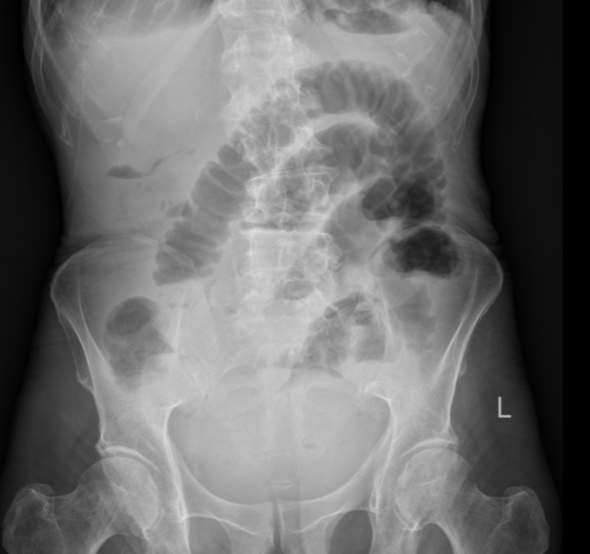

导管开始工作后,积聚的肠内容物被持续引出,腹胀腹痛的症状一天天缓解。老人的肠道功能慢慢恢复,复查腹平片显示梗阻情况明显好转。在护理团队的精心照料下,老人从卧床不起到能下地活动,从禁食禁水到逐渐恢复饮食,一天天好起来。2月24日,王大爷顺利出院,重新回归了正常生活。